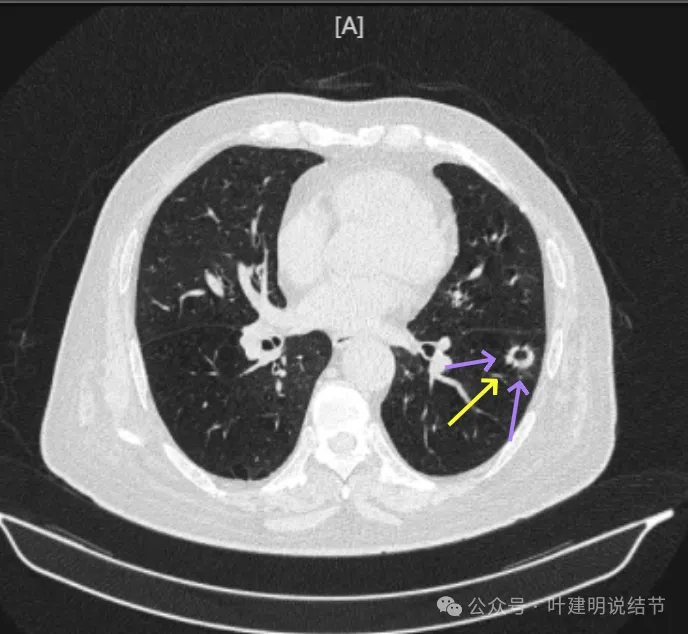

表面毛糙不平,部分区域有点像锯齿状。

表面不平细毛刺,中间空腔欠光滑、囊壁厚薄不均。

上图囊壁较厚,密度较高,轮廓与边界较清。

病灶边上也有多发小空泡样征,说明病灶有收缩力或对周围结构有影响。

上图显得像混合密度伴偏心空腔征。

上图是病灶边缘部位有血管走向病灶侧,并达病灶的地方有异常增粗。